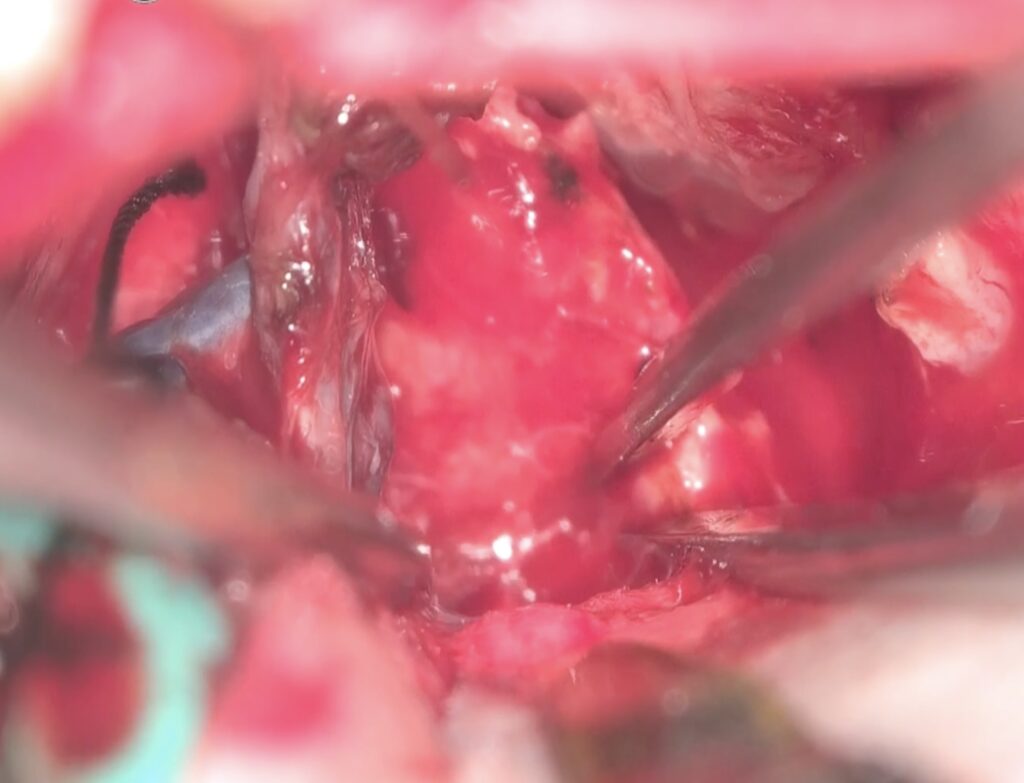

手術は通常通り行われ、顔面神経の麻痺を起こさずに摘出は終了し、うまくいったと考えていました。しかし術後より覚醒障害が続き、強い小脳腫脹を生じたため、術後脳室ドレナージ術、バルビタール麻酔療法、気管切開まで行い急性期を乗り切りました。術前より下肢静脈血栓症を合併していたことと、Petrosal veinが通常より広範囲の静脈環流を行っていたためと考えられます。現在、覚醒し、四肢が動くようになってきました。

手術は通常通り行われ、顔面神経の麻痺を起こさずに摘出は終了し、うまくいったと考えていました。しかし術後より覚醒障害が続き、強い小脳腫脹を生じたため、術後脳室ドレナージ術、バルビタール麻酔療法、気管切開まで行い急性期を乗り切りました。術前より下肢静脈血栓症を合併していたことと、Petrosal veinが通常より広範囲の静脈環流を行っていたためと考えられます。現在、覚醒し、四肢が動くようになってきました。